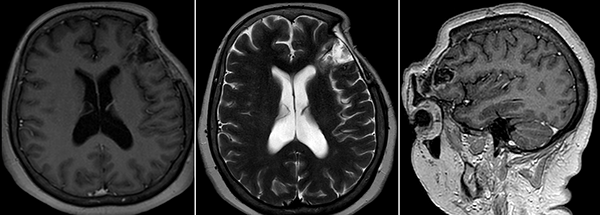

Concurrió con una radiografía (Rx) de cráneo frente y perfil donde se evidenció una lesión radiolúcida, circular y de bordes definidos con signos de remodelación esclerótica (Figura 1A y B). Tomografía computada (TC) de encéfalo mostró una lesión lítica de calota con deformación y esclerosis de la misma asociada a compromiso subgaleal, invasión intradural y extensión intraparenquimatosa en imagen de “reloj de arena” (Figura 1C y D).

Figura 1. A) y B) Rx de cráneo frente y perfil. C) y D) TC de cerebro sin contraste endovenoso.

Figura 2. RM de cerebro. A) Secuencia T1 sin contraste endovenoso. B) y C) Secuencia T1 con contraste endovenoso. D) Secuencia T2.

Resonancia magnética (RM) de encéfalo con contraste endovenoso evidenció una lesión heterogénea, predominantemente hipointensa en secuencia T1, hiperintensa en T2, heterogénea e isointensa con respecto al parénquima cerebral en Flair (Fluid attenuated inversión recovery), con escasas áreas de restricción en la secuencia difusión (DWI) y realce fino periférico tras la administración de contraste (Figura 2). Se observó efecto de masa leve con colapso de asta frontal de ventrículo lateral homolateral. Se realizó una angiotomografía de encéfalo para valorar la vascularización adyacente de la masa y descartar anomalías vasculares, siendo negativa para las mismas.